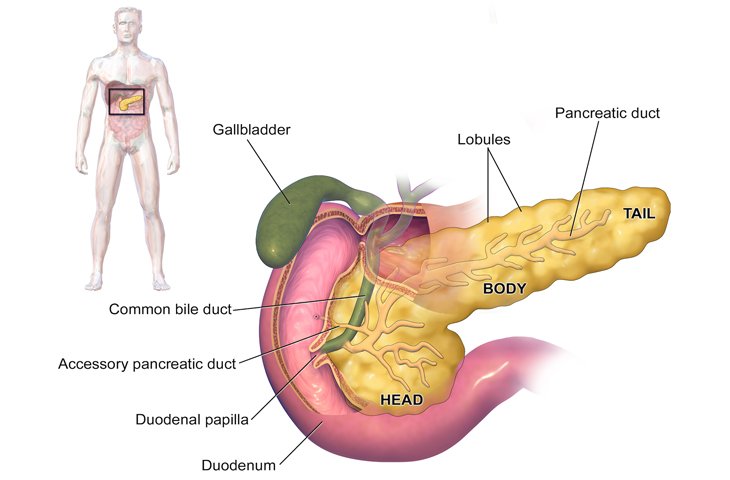

The pancreas is a leaf shaped organ or gland situated deep in the upper abdomen. It is part of the digestive system and produces important enzymes that help break down foods (exocrine function). It also has endocrine function (hormones directly released in blood stream) manly secretion of insulin. It is located in close proximity to stomach, duodenum and bile duct and major blood vessels which make it anatomically difficult to reach organ and make its surgery difficult which involve handling of near by organs also.